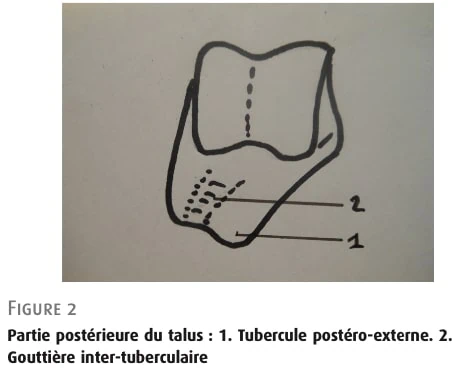

三叉骨

当距骨的次要骨化中心融合失败时,就会形成三棱锥骨(图 3)。 这种附属骨的发病率为 8-13%,双侧发病的比例略低于 2%。 其大小不一,但通常在 1 厘米以下;可能是两部分,甚至是碎裂的。 它通过一个关节突与距骨后侧面的结节相接,有时也与小腿骨的下表面相接。 足底屈曲时反复出现的微小创伤似乎会导致融合失败,这或许可以解释为什么在儿童时期就开始训练的足球运动员中融合失败的发生率较高。

图 3: 三叉骨。